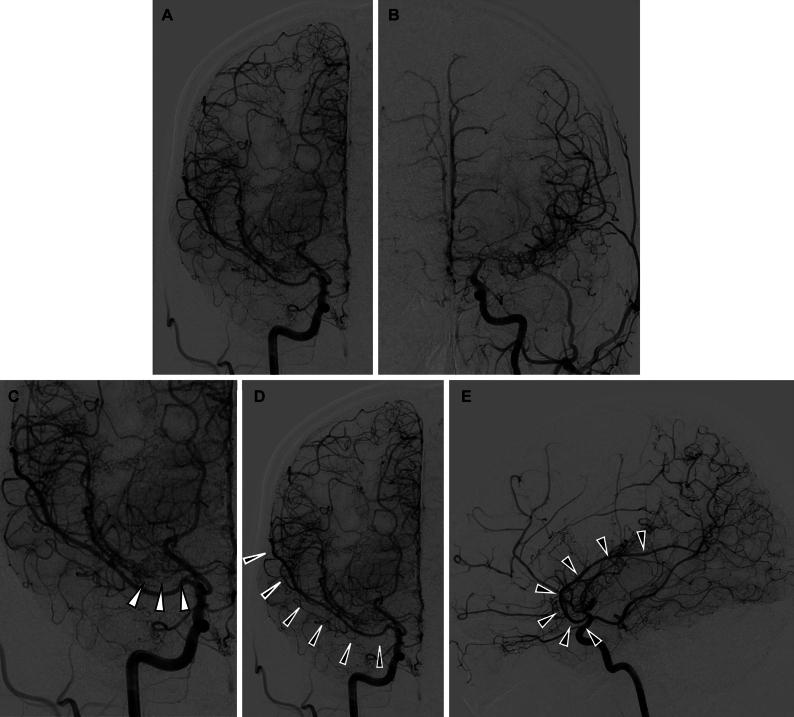

A 49-year-old Japanese woman diagnosed with MMD at 38 years of age was found to have a duplicated right MCA through digital subtraction angiography. Two years after the diagnosis, the vascular lesion progressed, leading to dropout of the right proximal anterior cerebral artery and disappearance of the bilateral anterior cerebral artery. She experienced a transient ischemic attack 2 years after the diagnosis and underwent bilateral revascularization. Eleven years of follow-up revealed no stenosis in either the MCA or ICA.

The progression of MMD may be attributed to shear stress that might have weakened the ICA distal to the duplicated MCA. Blood flow to the duplicated MCA was maintained, and the proximal ICA did not develop stenosis due to the preservation of shear stress. https://thejns.org/doi/10.3171/CASE2598.